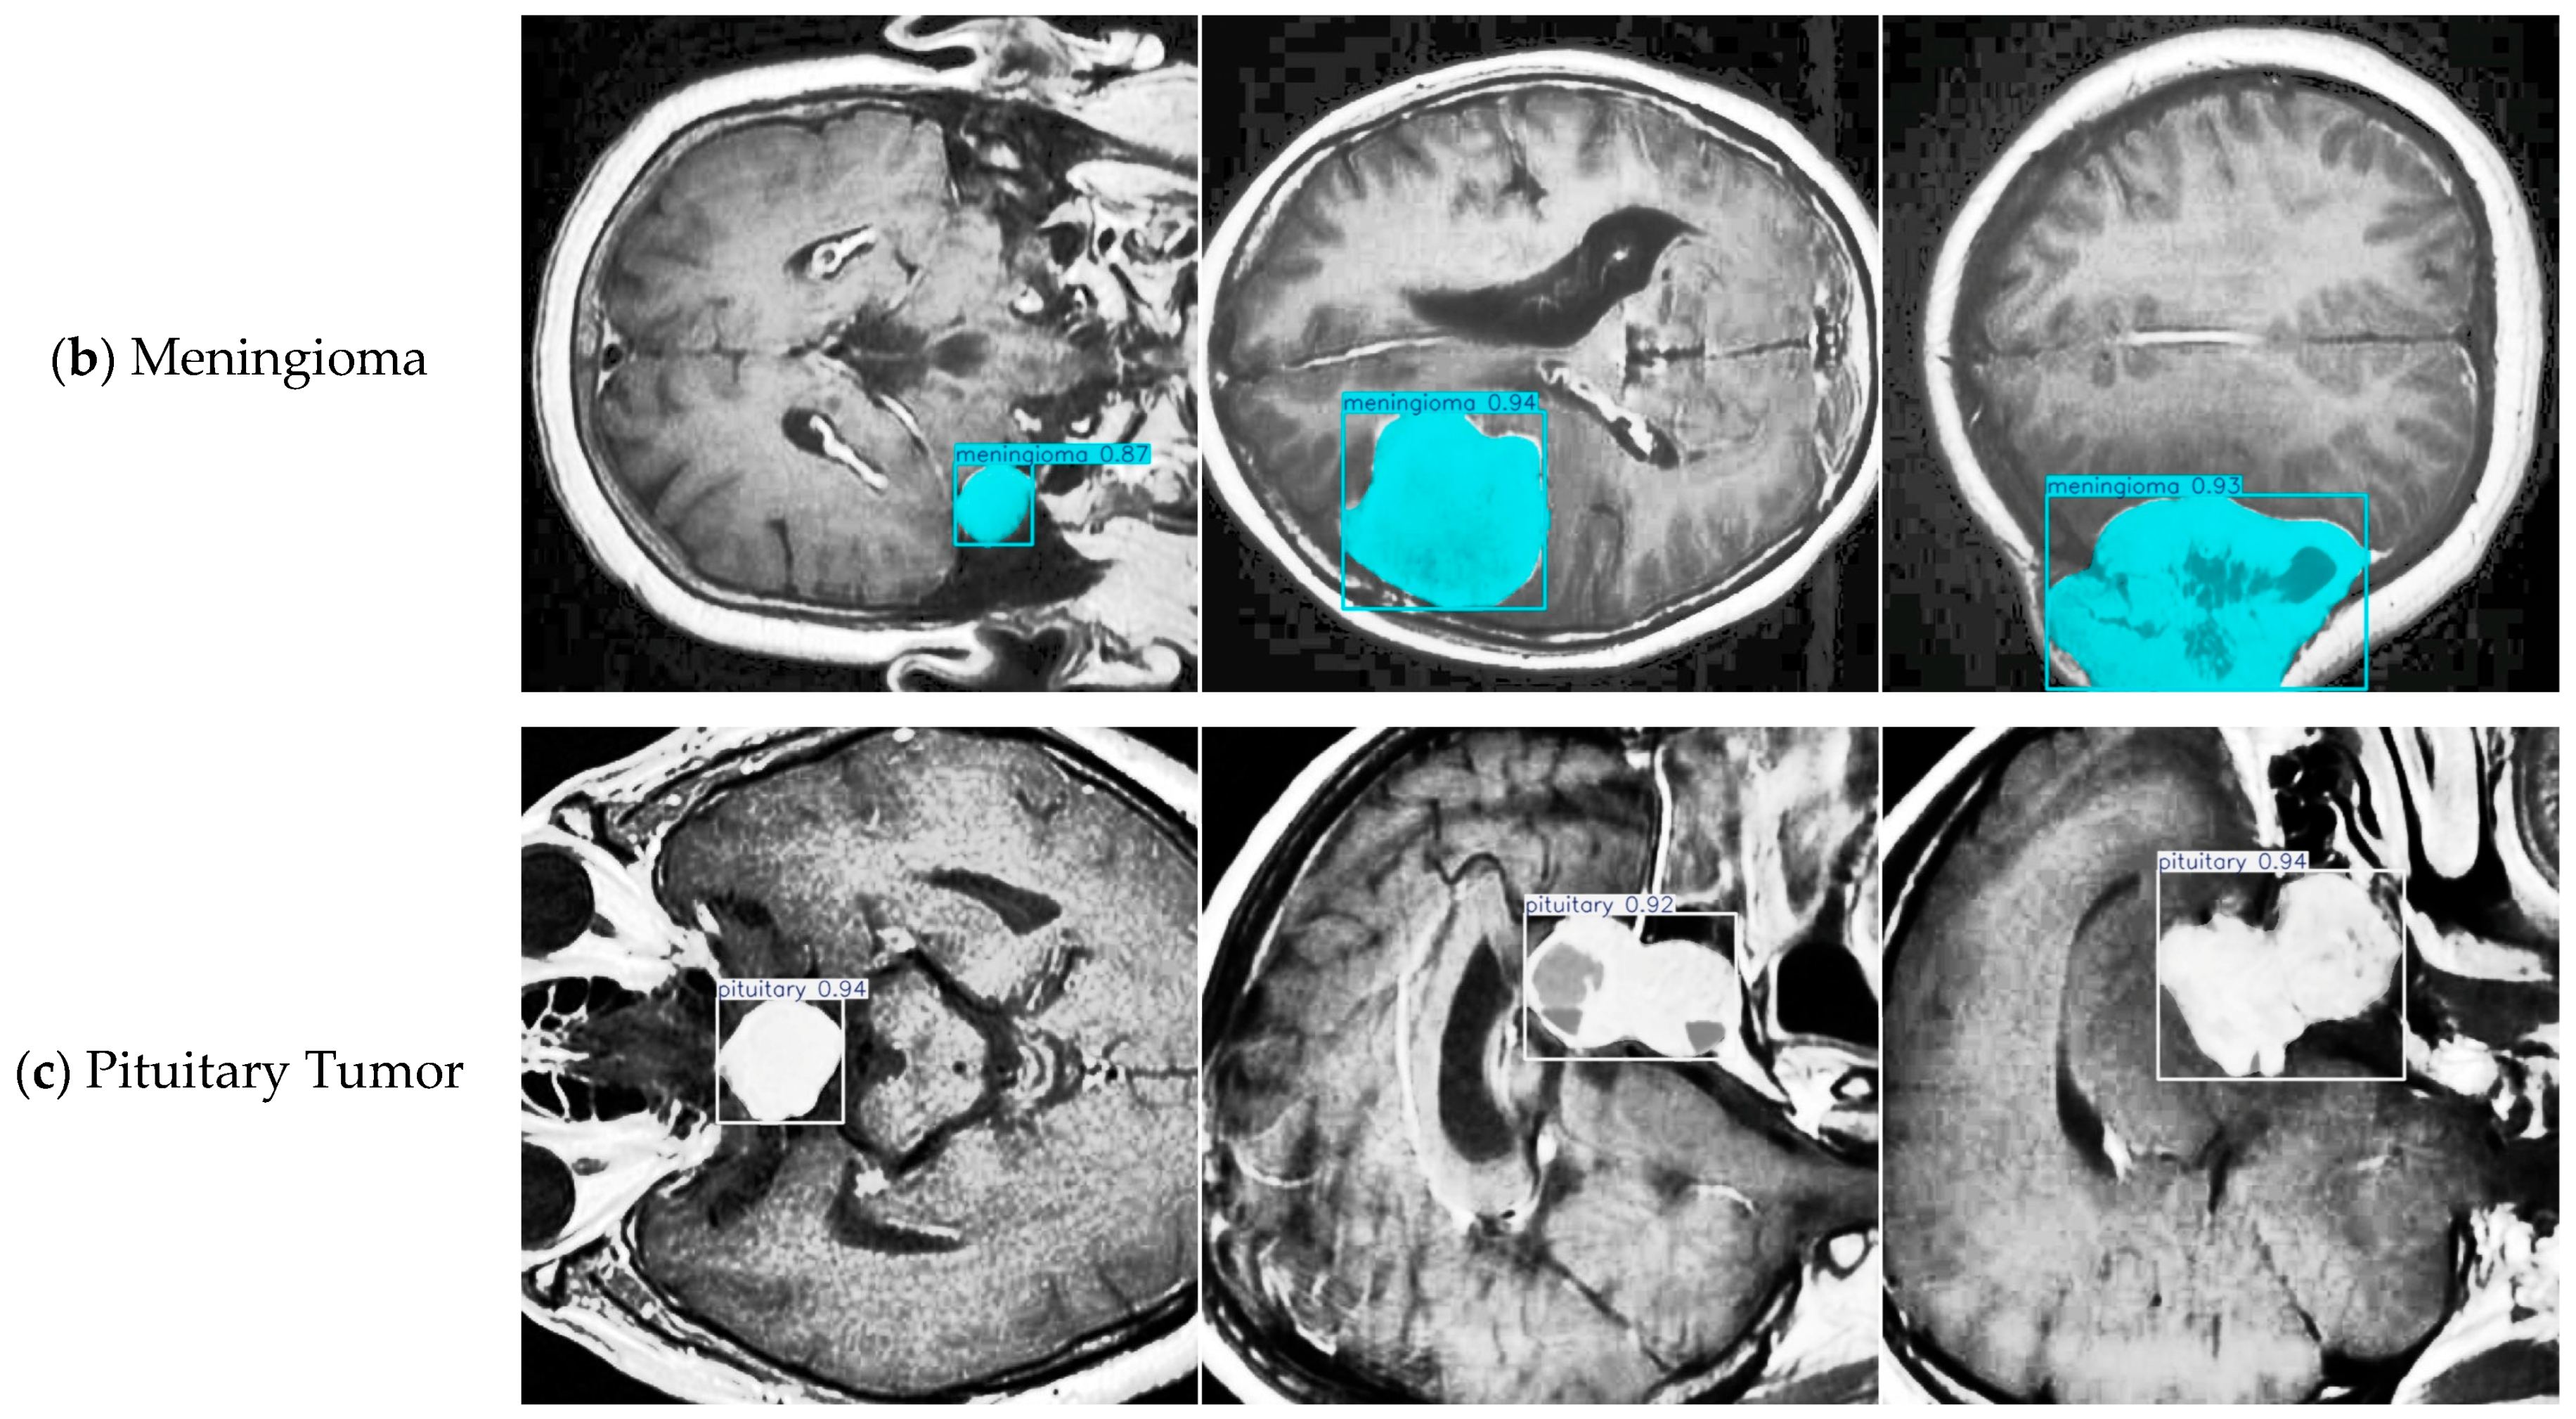

4.4. Model Training, Testing, and Results Analysis

| Class | FALS-YOLO Correct Classification | FALS-YOLO Misclassification | YOLOv8-Seg Correct Classification | YOLOv8-Seg Misclassification |

|---|---|---|---|---|

| Glioma | 132 | 40 | 124 | 37 |

| Meningioma | 58 | 10 | 56 | 6 |

| Pituitary | 81 | 10 | 78 | 5 |

| Background | - | 31 | - | 42 |